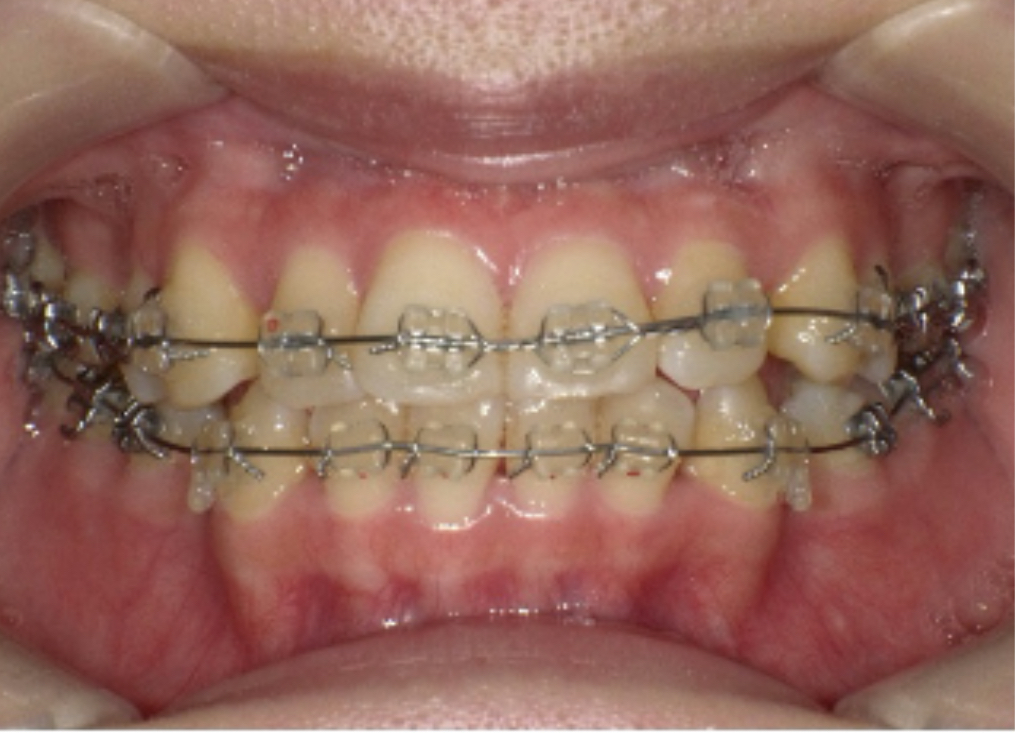

特にワイヤー矯正の場合、ブラケット周囲にプラークが残ると「白い輪状の虫歯(脱灰)」ができやすくなります。

そのため、歯磨きはもちろん、定期的なプロフェッショナルクリーニングが欠かせません。